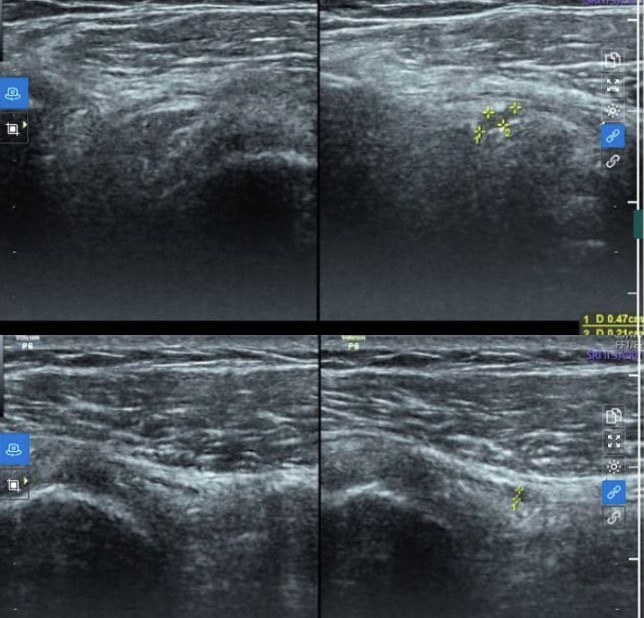

| Hình ảnh tổn thương được phát hiện trên siêu âm khớp vai. |

Tại đây, sau khi thăm khám lâm sàng, bác sỹ chỉ định thực hiện các kỹ thuật cận lâm sàng cần thiết phục vụ chẩn đoán. Đáng chú ý, hình ảnh siêu âm khớp vai phải bằng đầu dò tần số cao cho thấy tình trạng rách bán phần gân cơ trên, kèm theo ít dịch trong túi hoạt dịch dưới cơ Delta.

Chẩn đoán xác định cho thấy bệnh nhân bị rách bán phần gân trên gai, kèm viêm bao thanh dịch dưới cơ Delta vai phải. Bệnh nhân được chỉ định điều trị bằng phương pháp tiêm huyết tương giàu tiểu cầu tại vị trí rách gân trên gai và bao thanh dịch dưới cơ Delta vai phải dưới hướng dẫn siêu âm.